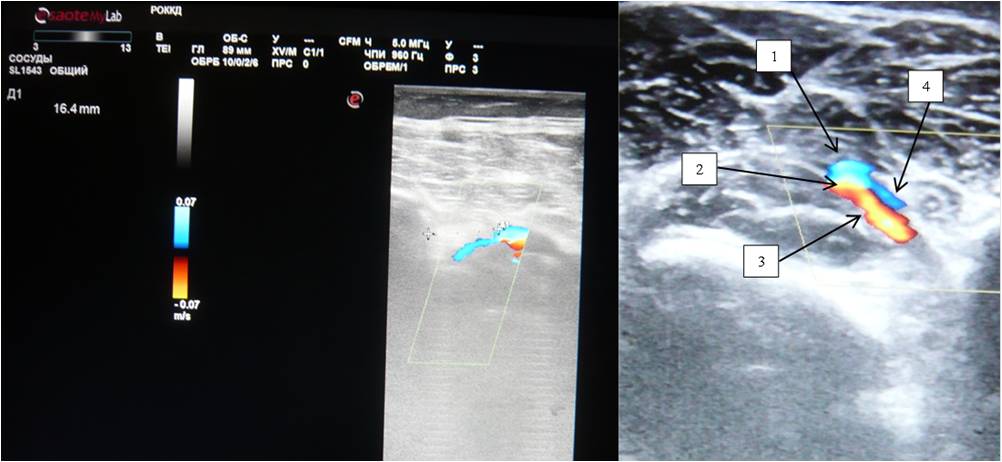

The sural veins were visualized in all patients, usually two on the medial and lateral surfaces, forming a single trunk before joining the PV and located at the sides of the sural arteries. It is important to note that the sural artery is a fairly large vessel, 2.8 ± 0.3 mm in diameter, which suggests its significant role in the development of collateral circulation in patients with peripheral atherosclerosis (Figure 6).

Fig. 6. Duplex scan of the sural artery; (A) B-mode; (B) Color Doppler mapping mode; (C) Spectral Dopplerography mode.

Notes: (1) Popliteal artery; (2) Sural artery.